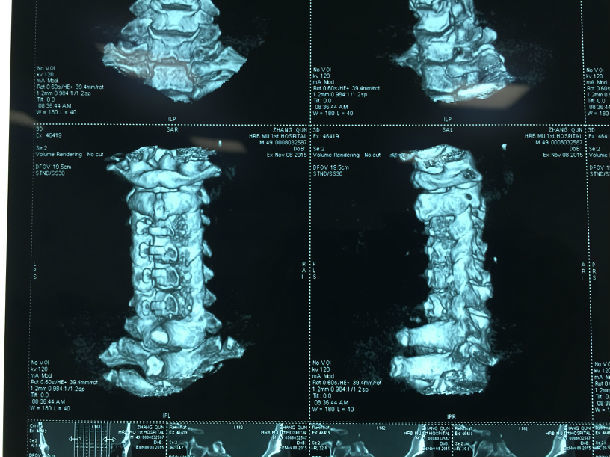

显微镜下微创手术后-颈椎管明显增宽/脊髓受压解除/患者症状迅速好转

显微镜下经颈后路行单开门椎管扩大成形术-颈椎管明显增宽/脊髓受压解除/患者逐渐康复